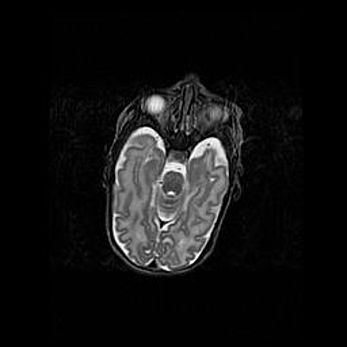

Множественные мелкие кисты перивентрикулярной области.

Киста прозрачной перегородки.

Возраст: 28 дней

Вес: 2400 г

Пол: женский

Окружность головы: 33 см

Срок гестации: 34 недели

Перивентрикулярная киста – это полостное образование в околожелудочковых областях белового вещества головного мозга. С морфологической точки зрения – это мелкоочаговая зона коагуляционного некроза, возникшая после инфаркта белого вещества. Наиболее часто поражаются начальные отделы задних рогов боковых желудочков. Обычно образования заполнены жидкостным содержимым.

Киста прозрачной перегородки может располагаться в переднем отделе межжелудочковой перегородки, в области мозолистого тела и мозжечка.